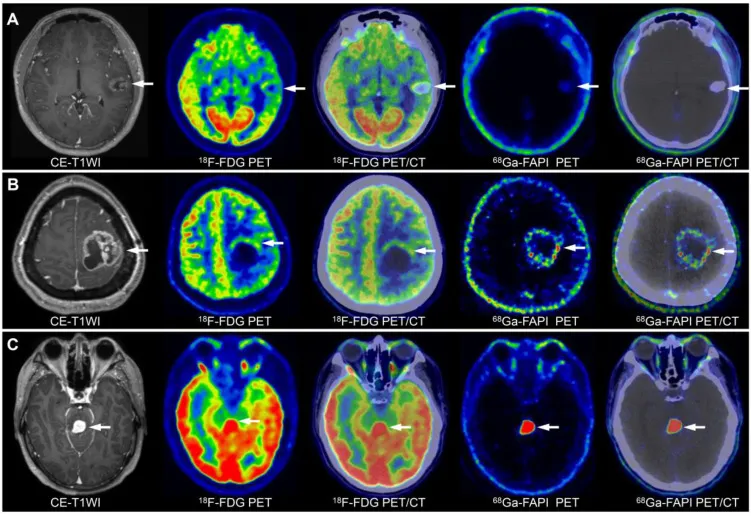

不同级别胶质瘤影像特征:A,低级别胶质瘤;B,三级胶质瘤;C,司机胶质瘤。